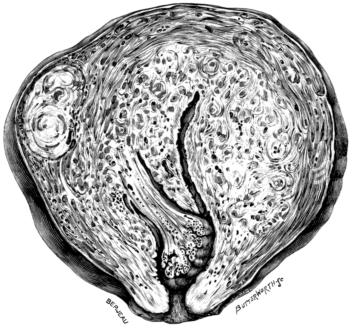

| 23. | A Gravid Uterus in Sagittal Section | 79 |

| 28. | A Uterus in Sagittal Section | 119 |